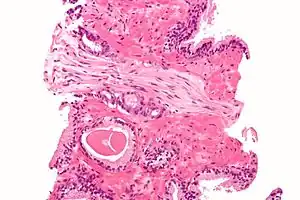

Each axon is surrounded by a layer of connective tissue called the endoneurium. The axons are bundled together into groups called fascicles, and each fascicle is wrapped in a layer of connective tissue called the perineurium. The entire nerve is wrapped in a layer of connective tissue called the epineurium. Nerve cells (often called neurons) are further classified as either sensory or motor.

Structure

Each nerve is covered on the outside by a dense sheath of connective tissue, the epineurium. Beneath this is a layer of fat cells, the perineurium, which forms a complete sleeve around a bundle of axons. Perineurial septae extend into the nerve and subdivide it into several bundles of fibres. Surrounding each such fibre is the endoneurium. This forms an unbroken tube from the surface of the spinal cord to the level where the axon synapses with its muscle fibres, or ends in sensory receptors. The endoneurium consists of an inner sleeve of material called the glycocalyx and an outer delicate meshwork of collagen fibres.[2] Nerves are bundled and often travel along with blood vessels, since the neurons of a nerve have fairly high energy requirements.